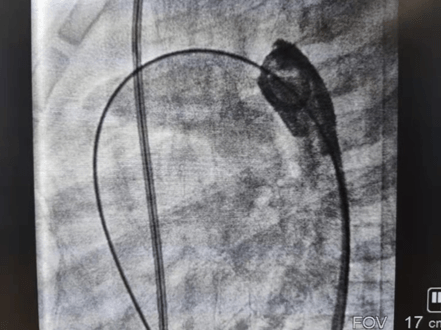

2021年11月12日,延安大学咸阳医院心血管病院吴栋梁院长、李阳主任介入团队为一例年仅13个月的女性患儿进行了先天性心脏病动脉导管未闭介入封堵手术。这是我院迄今为止介入封堵治疗年龄最小、体重最轻的患儿,手术过程顺利,封堵成功,解决了一家人的痛苦,患儿术后恢复良好,于2021年11月17日顺利出院。

先天性心脏病发病率已逐年下降,但因我国人群基数大,所以患者并不少见,先天性心脏病也是心血管疾病中为数不多的可通过介入或者外科手术得到根治的疾病之一,一般手术多建议在3岁以后进行,3岁以内患儿因体重太小,对患儿进行动静脉穿刺置管、手术操作过程及麻醉难度明显增加。该患儿体重仅10kg,身高仅70cm多一点,因动脉导管分流量较大,影响患儿发育,反复因肺部感染诱发心衰,并已经出现左房左室扩大,需尽早手术,否则出现心衰加重可能错过手术时机,但患儿家属对外科开胸心存畏惧,而且外科手术后胸部手术瘢痕明显影响女性患者的美观,通过多方打听,患儿联系到了何克强医生、李阳主任及吴栋梁院长手术团队,家属对医生期望值极高,因患儿情况特殊,吴栋梁院长及心血管内科五病区团队术前对患儿手术情况进行讨论,制定严密的手术方案,对手术中可能出现的难点进行充分的准备,最终在穿刺及麻醉成功后1小时内便顺利完成手术,此例手术的开展,标志着我院在先心病介入治疗方面再上新台阶,患儿术后恢复非常好,得到了患儿家属的肯定,解决了患儿一家的困扰。